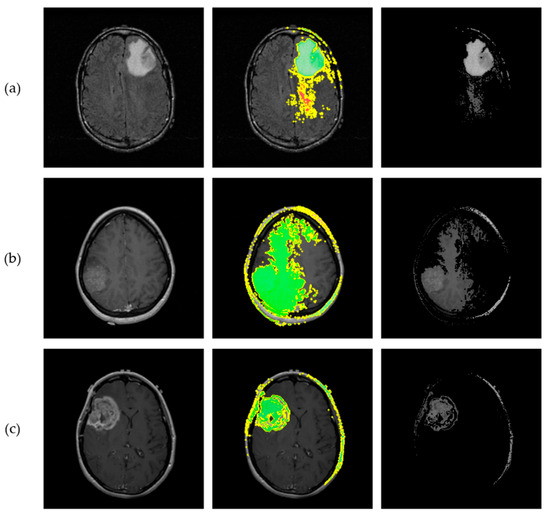

Deep learning models for three-dimensional (3D) data are increasingly used in domains such as medical imaging, object recognition, and robotics. At the same time, the use of AI in these domains is increasing, while, due to their black-box nature, the need for explainability has grown significantly. However, the lack of standardized and quantitative benchmarks for explainable artificial intelligence (XAI) in 3D data limits the reliable comparison of explanation quality. In this paper, we present a unified benchmarking framework to evaluate both intrinsic and post hoc XAI methods across three representative 3D datasets: volumetric CT scans (MosMed), voxelized CAD models (ModelNet40), and real-world point clouds (ScanObjectNN). The evaluated methods include Grad-CAM, Integrated Gradients, Saliency, Occlusion, and the intrinsic ResAttNet-3D model. We quantitatively assess explanations using the Correctness (AOPC), Completeness (AUPC), and Compactness metrics, consistently applied across all datasets. Our results show that explanation quality significantly varies across methods and domains, demonstrating that Grad-CAM and intrinsic attention performed best on medical CT scans, while gradient-based methods excelled on voxelized and point-based data. Statistical tests (Kruskal–Wallis and Mann–Whitney U) confirmed significant performance differences between methods. No single approach achieved superior results across all domains, highlighting the importance of multi-metric evaluation. This work provides a reproducible framework for standardized assessment of 3D explainability and comparative insights to guide future XAI method selection.